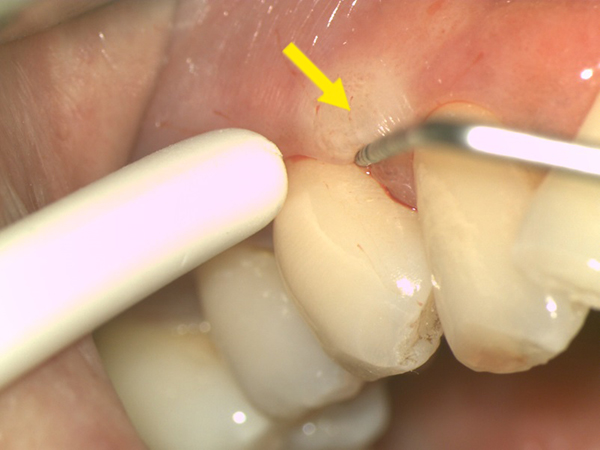

顯微鏡下進行牙周病治療,使用高倍數醫療顯微鏡,360度檢查每顆牙齒牙周狀況,紅色箭頭處可見造成牙周病主因的牙齦下牙結石,使用特殊顯微超音波工具清除後,可見乾淨的牙根表面,幾無出血(黃色箭頭處)。

治療前![]() |

治療後![]() |

*以上醫師案例僅供參考;患者應依醫師個別評估結果為準。*

雄高信合美牙醫 牙周病科呂婷醫師 臨床案例提供